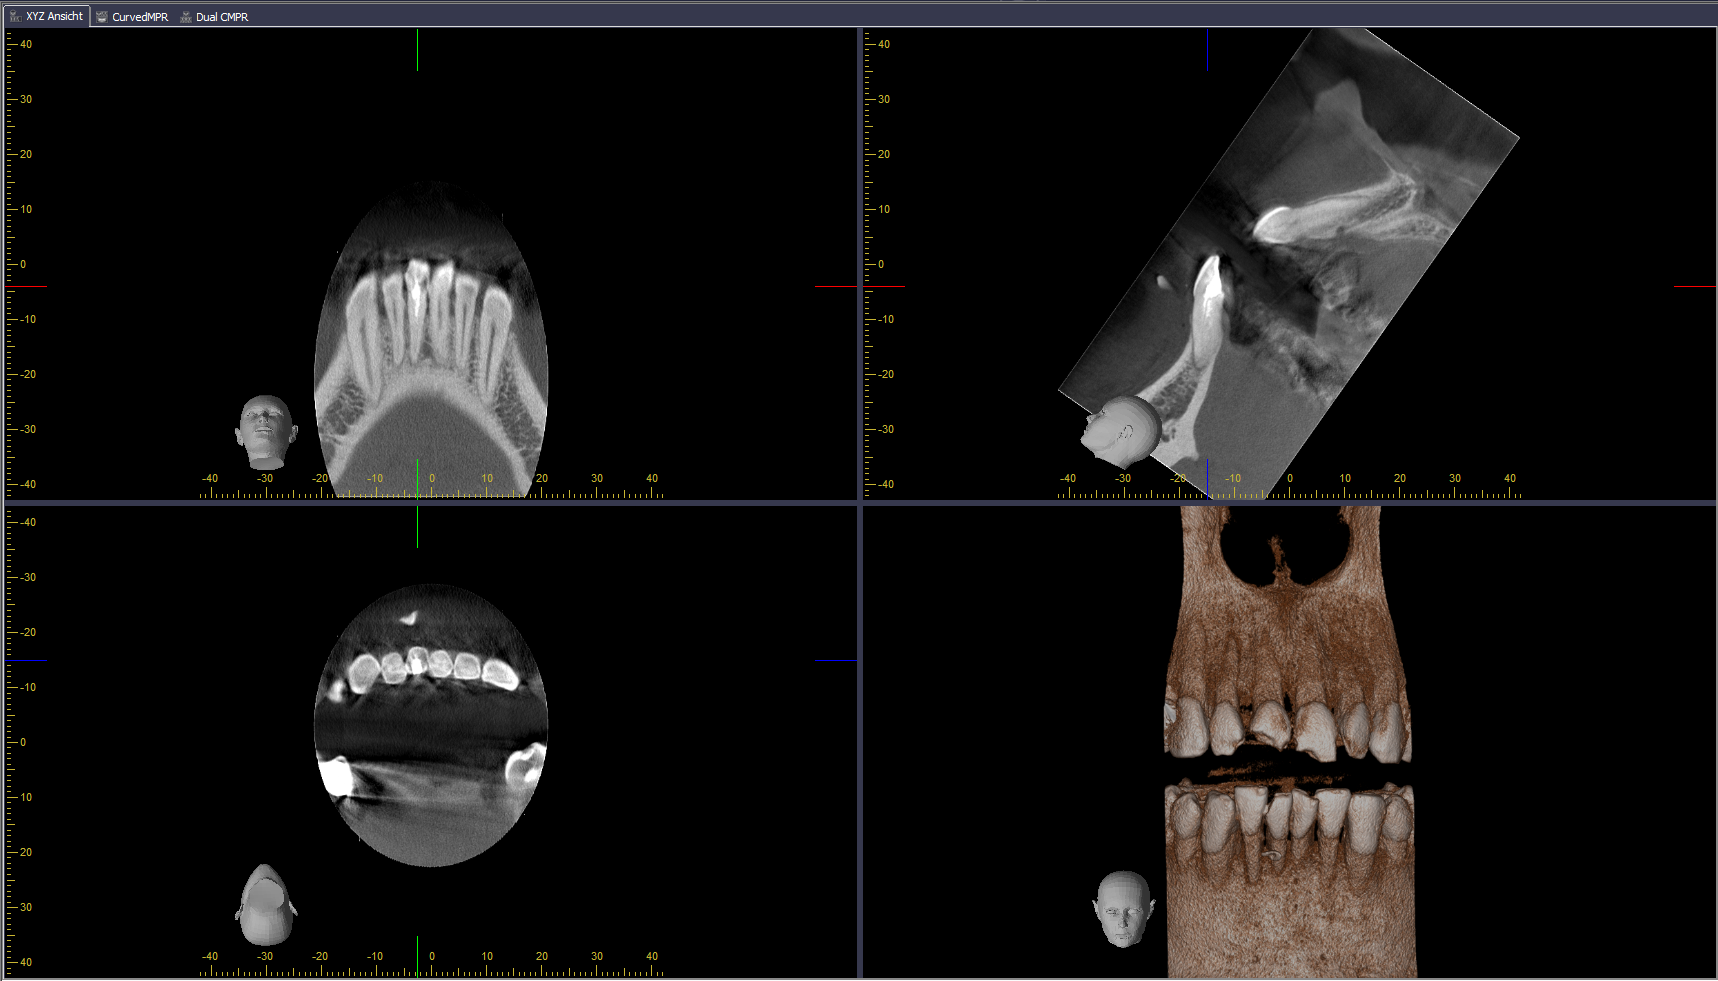

Bildschirmfoto 2015-07-20 um 17.28.42 Veröffentlicht 20. Juli 2015 am 1718 × 981 in Röntgenbefund (2)